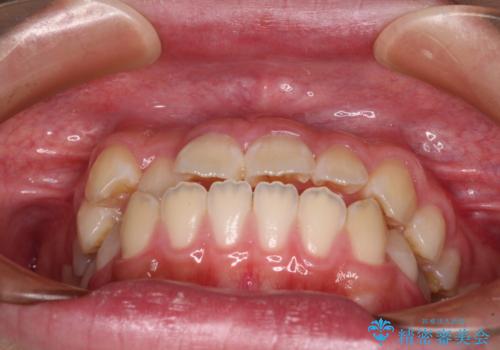

- 前歯が開いて飛び出していることを気にして来院された患者様です。

舌の突出癖により上下前歯は接触できず、更には前方に押し出されて出っ歯になっている状態でした。

上下左右の第一小臼歯4本を抜歯し、ワイヤー装置での抜歯矯正を行っていくのですが、原因である舌の突出癖を改善しないことには治療がうまく進められないため、舌のトレーニングを徹底するよう指導していくこととしました。